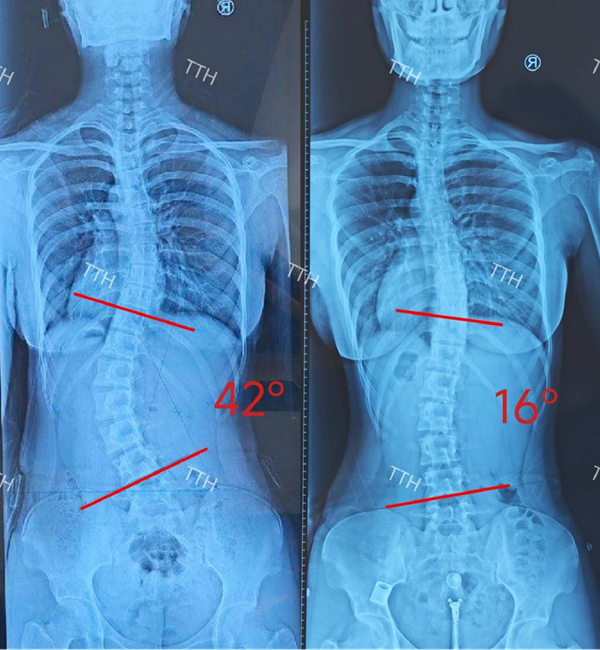

半岛网4月3日讯 “孩子越长大越驼背,肩膀也一高一低,连穿衣服都自卑,我们跑了好几家医院,都没能改善!”12岁的朵朵(化名)被查出脊柱侧弯已有两年,侧弯度数逐渐加重至42°,家长带着她辗转求医,始终未能打破“只治脊柱、忽略根源”的诊疗困局,直到遇见海顾医疗踏踏虎儿童足脊健康管理团队,这场困扰全家的成长烦恼才终于迎来转机。凭借国内领先的足脊一体化生物力学矫正技术,团队为朵朵定制个性化诊疗方案,成功帮助她矫正脊柱侧弯,重拾挺拔身姿,也让踏踏虎成为区域青少年脊柱侧弯治疗的标杆,续写海顾医疗守护儿童成长的初心。

据悉,朵朵上小学四年级时,家长偶然发现她站立时双肩不等高、背部不对称,前往医院检查后,被确诊为特发性脊柱侧弯,度数为20°。起初,家长仅仅通过网络上的视频带孩子进行单纯的“训练操”,也参加过十几个孩子一起做训练的所谓“训练营”,可坚持两年后,侧弯度数不仅没有控制,反而上升至42°,孩子非常失望,出现自卑的情况,开始回避社交,性格也变得内向敏感。

经过一年多的规范矫正,朵朵的脊柱侧弯度数从42°降至16°,双肩恢复平齐,背部线条变得挺拔,走路也不再容易疲劳,性格也变得开朗自信,重新主动参与学校的文体活动。“以前总怕别人盯着我的后背看,现在终于能抬头挺胸走路了,太感谢踏踏虎的专家团队了!”朵朵的脸上重新绽放出灿烂的笑容。